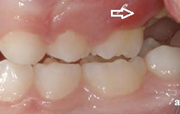

Lutipudelikaariese kahjustused

Lutipudelikaaries